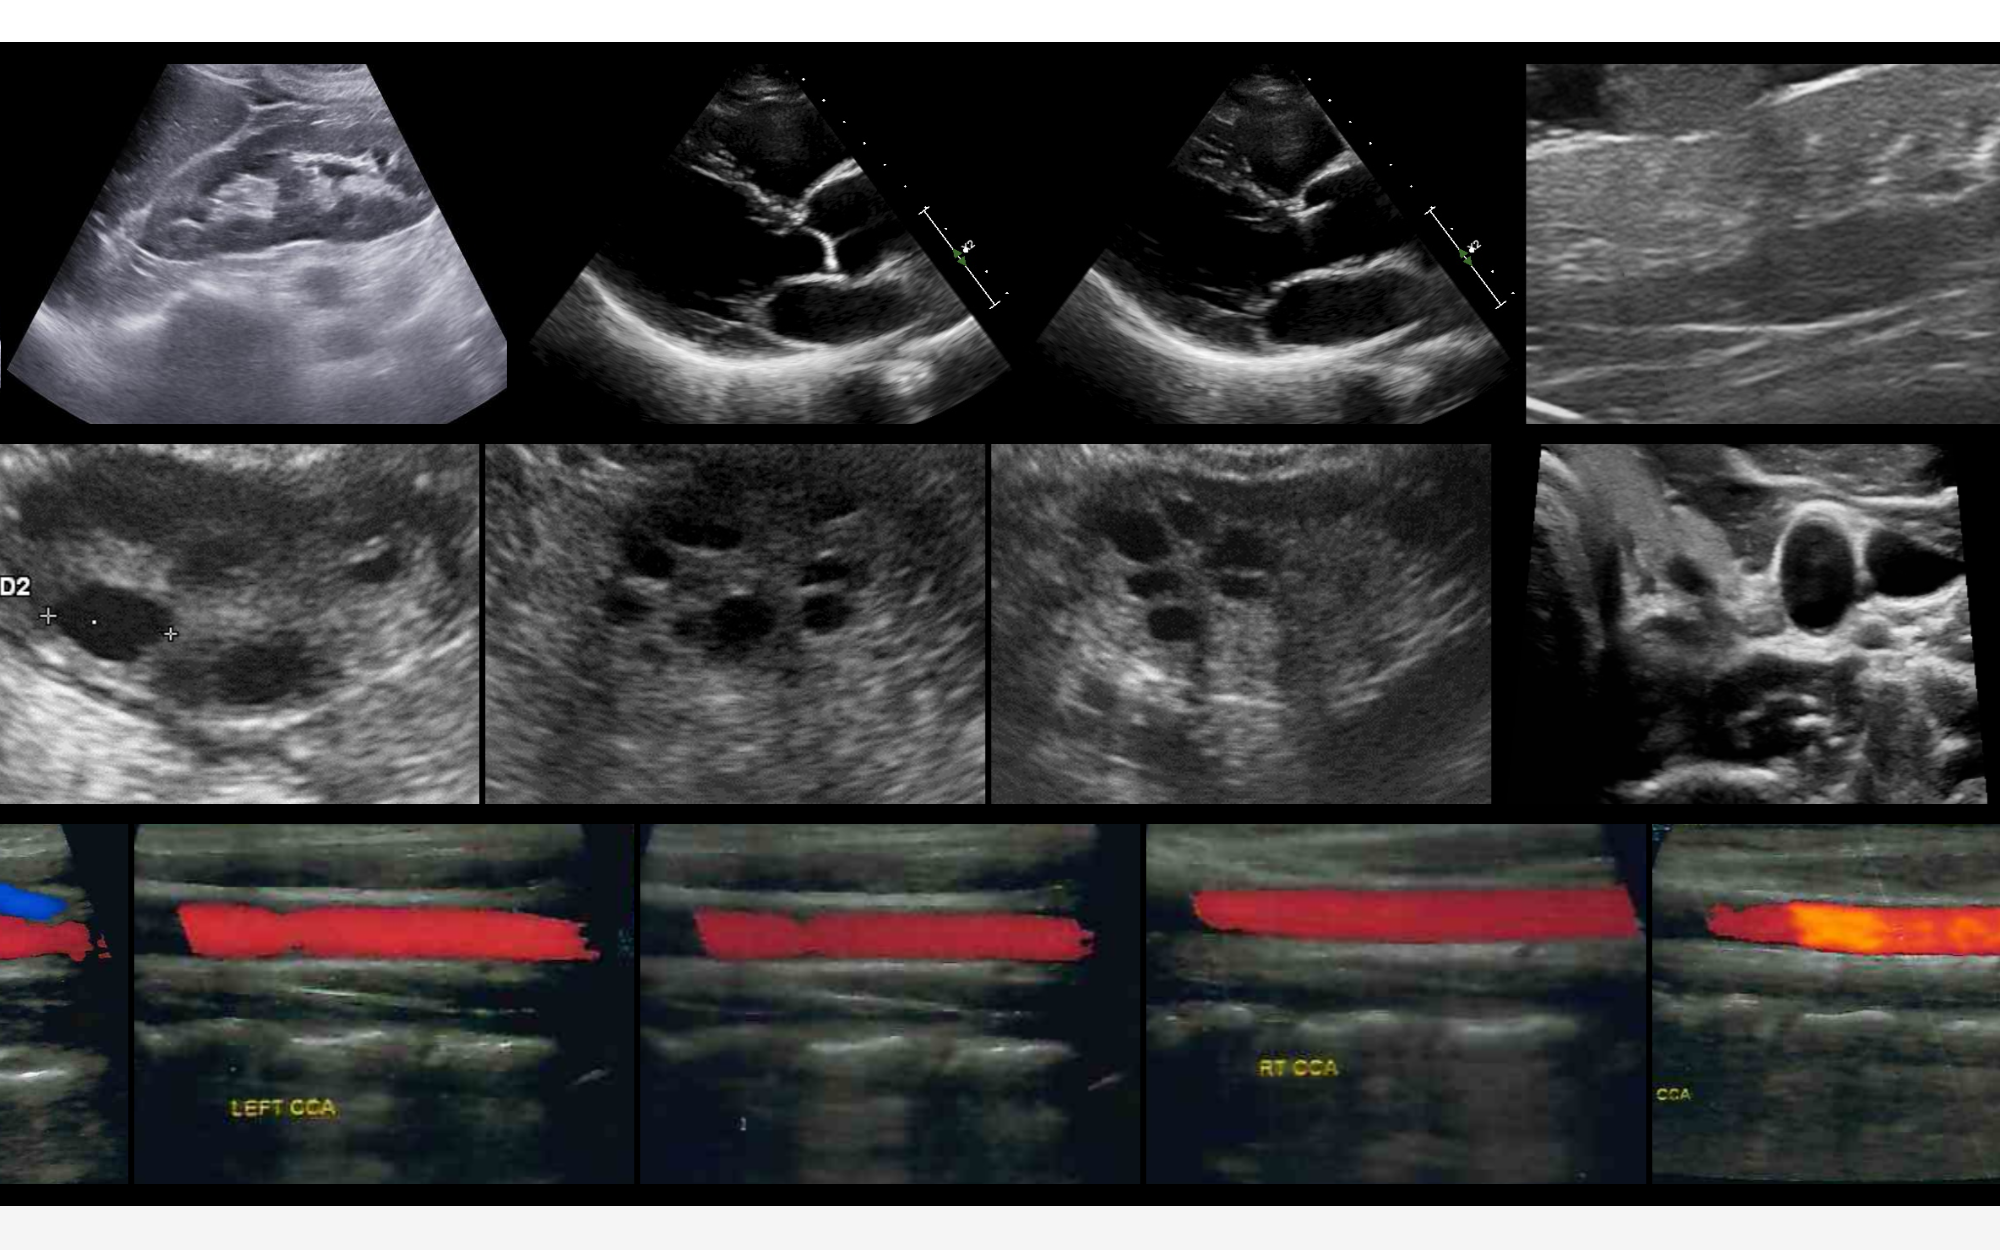

聆音EchoCare是由中国科学院香港创新研究院人工智能与机器人创新中心(CAIR)研发的超声基座大模型,于2025年9月17日正式开源发布。该模型基于全球已知规模最大的超声影像数据集(超过450万张图像,涵盖50多个人体器官)训练而成,旨在解决传统超声AI模型对大规模标注数据的依赖、长尾分布处理困难、泛化性不足及医学知识嵌入困难等问题。通过首创的结构化对比自监督学习框架和层级化双分支架构,聆音在器官识别、分割、病灶分类等10余项超声医学任务中性能全面登顶,为超声AI的规模化应用和临床落地提供了创新解决方案。

- 多任务高性能:在器官识别、分割、病灶分类、关键点检测、切面识别等10余项任务中表现卓越,性能平均优于当前最优方法(SOTA)3%-5%。

- 临床适配性:单张图像分析时间小于0.5秒,支持实时诊断;输出分割掩码、热力图等可视化结果,并可自动生成诊断报告(BLEU-4评分达78.47)。

- 心脏超声检测:支持主动脉瘤检测、左心室射血分数计算等任务。